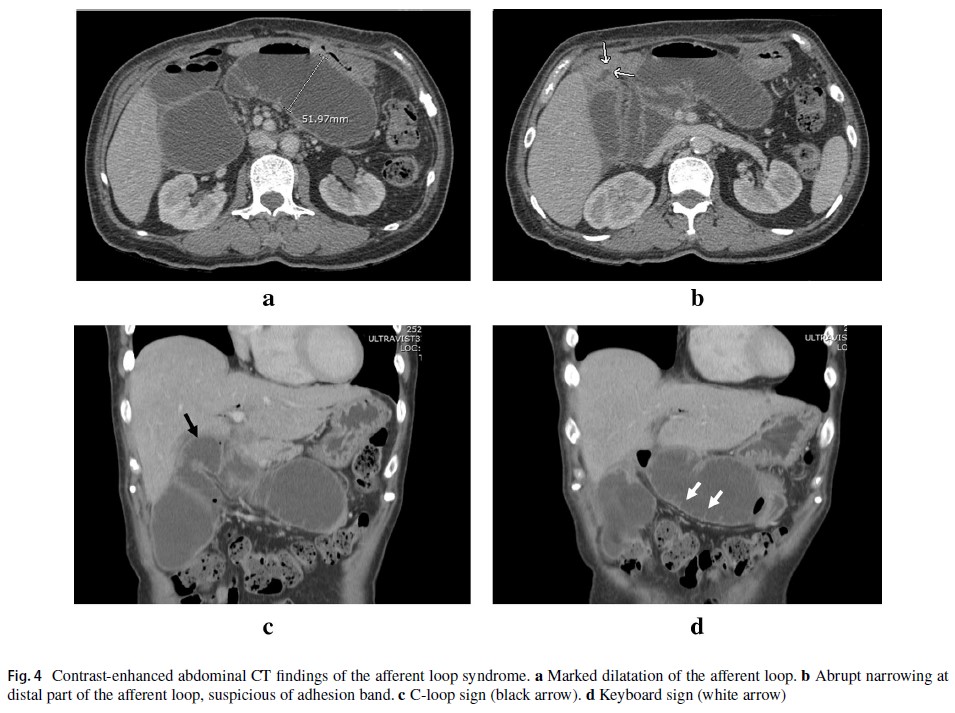

Termsinsuk P, Chantarojanasiri T, Pausawasdi N. Diagnosis and treatment of the afferent loop syndrome. Clin J Gastroenterol. 2020 Oct;13(5):660-668.